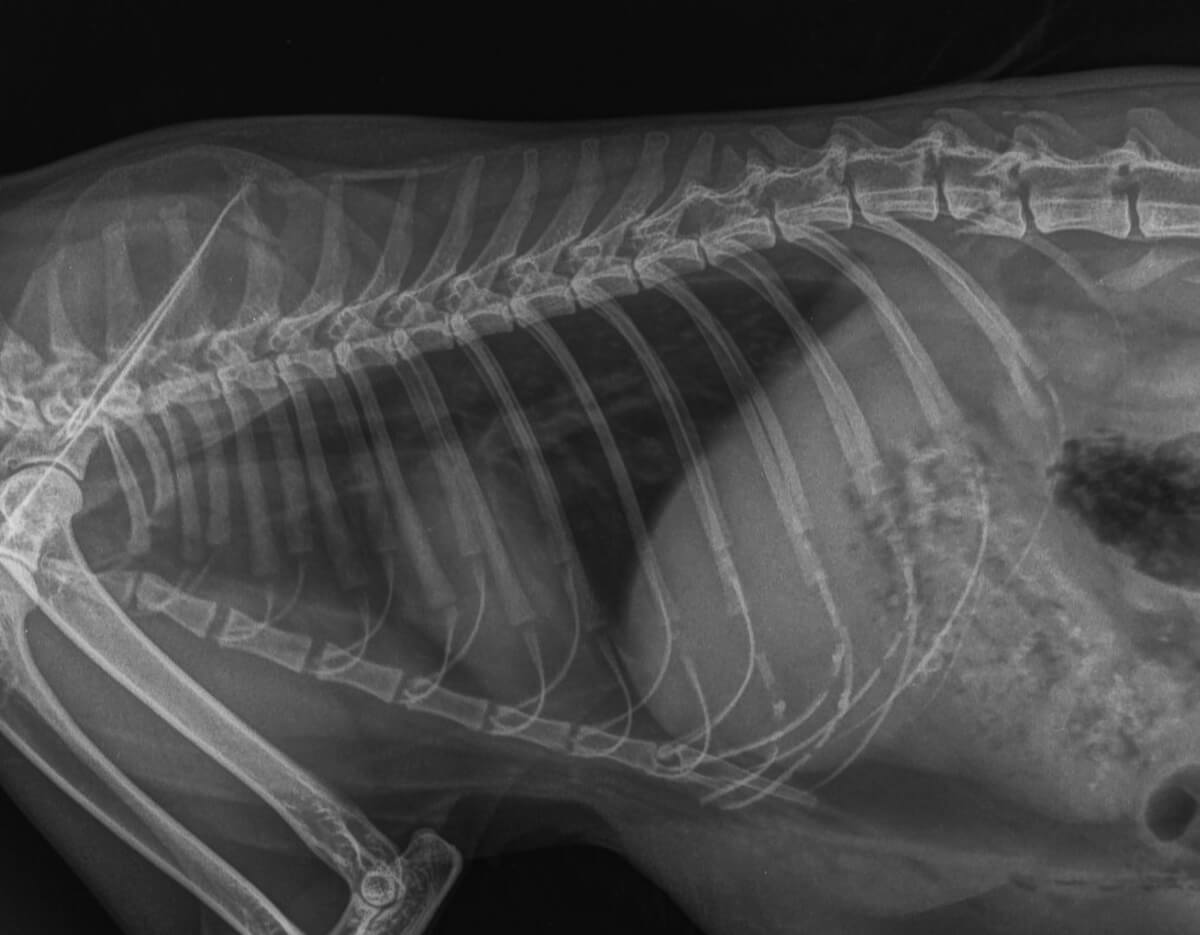

La neumonía es una enfermedad que afecta a los pulmones debido a la presencia de diferentes microorganismos. Según el germen presente, la zona afectada o la causa, será denominada de una forma y tendrá un tratamiento específico.

Sintomatología

Antes de poder identificar la enfermedad, es necesario observar los síntomas que manifiesta el perro. De esta manera, se le podrán relatar al veterinario, quien considerará si son importantes o no, siendo algunos de ellos:

- Tos frecuente y húmeda.

- Fiebre.

- Deshidratación.

- Pérdida de apetito.

- Cansancio.

- Producción de secreciones mucosas.

- Emisión de sonidos al respirar.